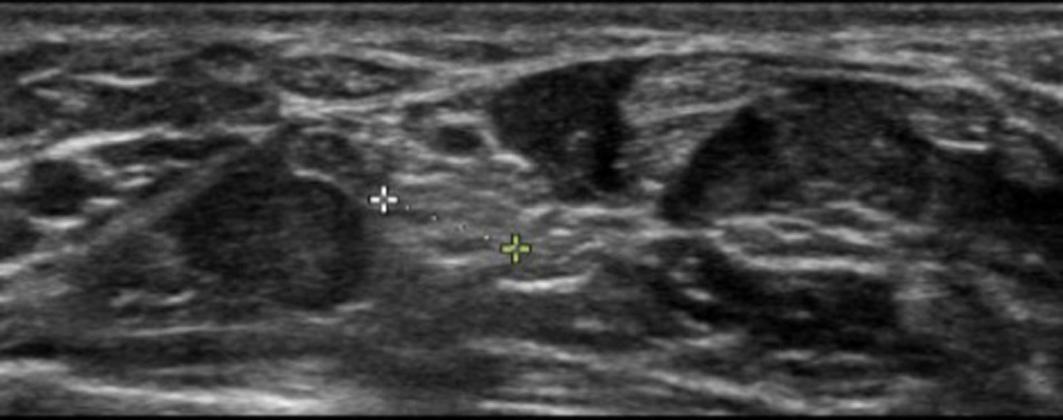

sustainedabitetohisleftthumbfromapetdog.Thedogwas fullyvaccinatedandhadnotbeendemonstratingabnormal behaviorsleadinguptotheincident.Onarrivalthepatient appearedacutelyill.Vitalssignswerenotableforaheartrate of108beatsperminute,bloodpressureof78/43millimeters ofmercury,tachypneaatarateof38breathsperminute,and atemperatureof36.3° Celsius.Examinationoftheulnar aspectoftheleftthumbrevealedtwofaint,punctatebite marksthatlaterbecameduskyandlocallynecrotic (Image1).Darkpurple,non-blanchingmaculeswereseenin allextremitiesconsistentwithpurpurafulminansandhighly suggestiveof Capnocytophaga septicemia(Image2).

Image1. Lefthandwithpurpuraandlocalnecrosis(arrows)as wellaspetechiae(asterisk).